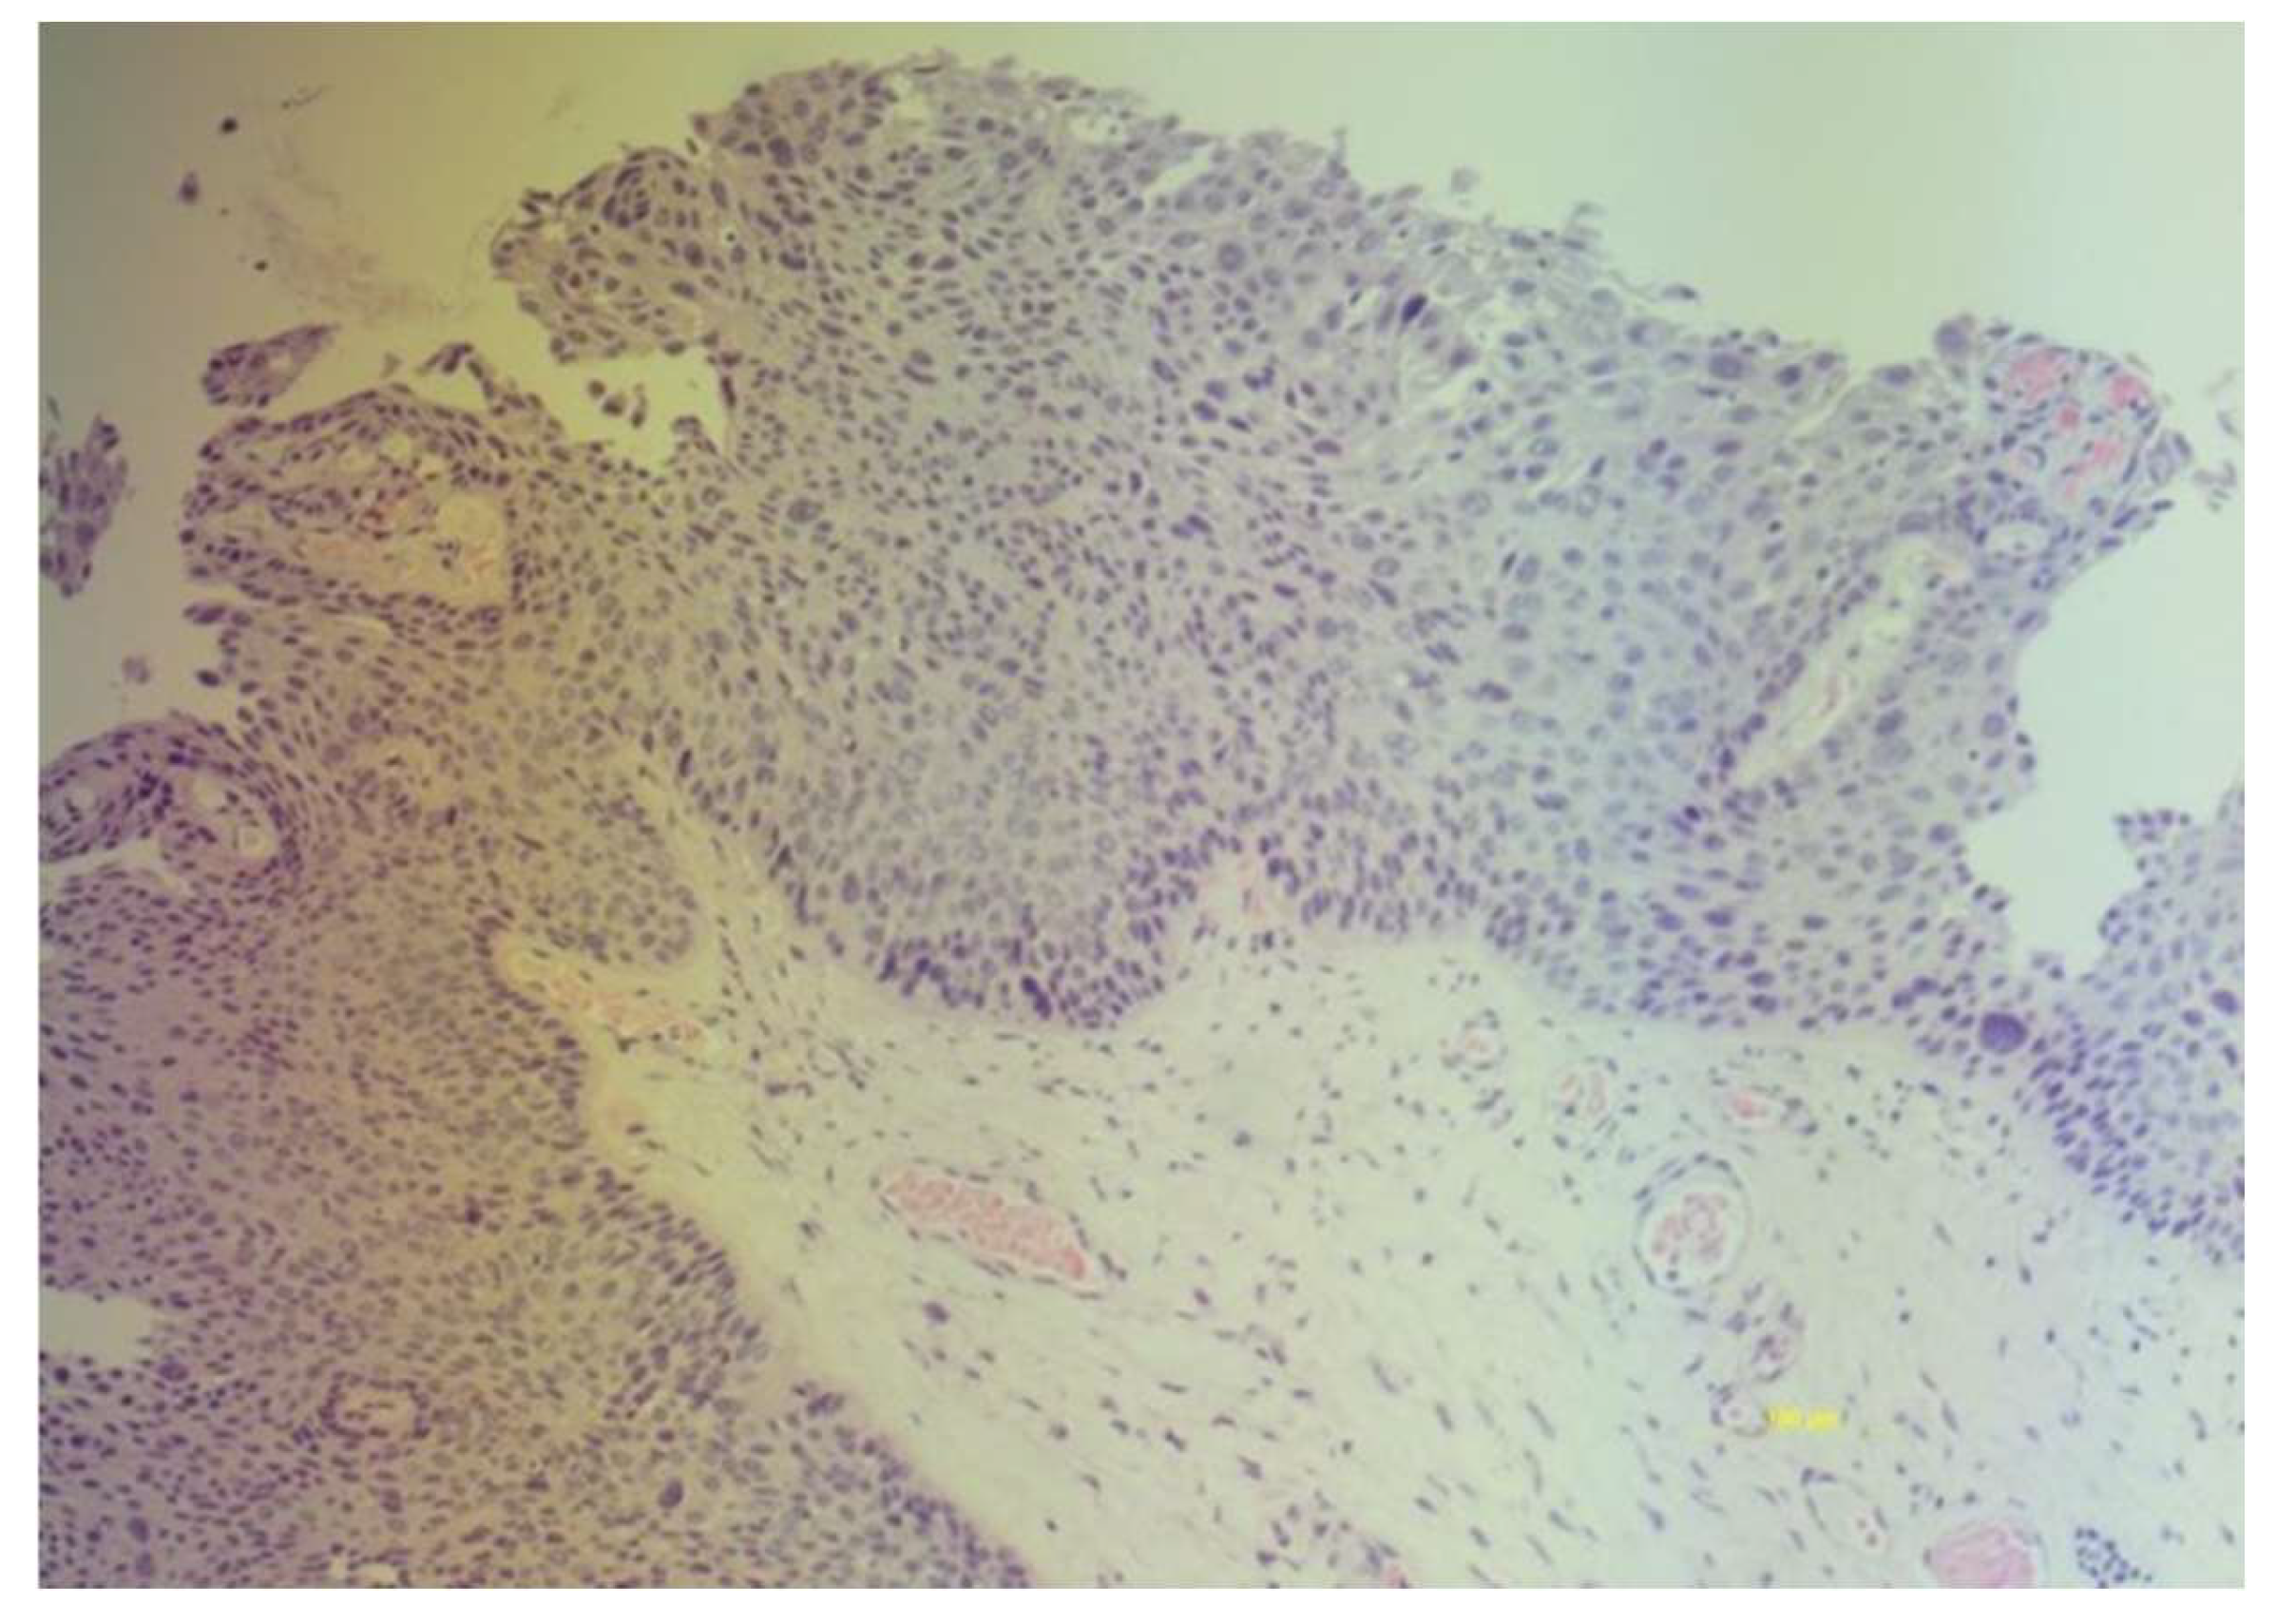

- Darragh TM, Colgan TJ, Thomas Cox J, Heller DS, Henry MR, Luff RD, McCalmont T, Nayar R, Palefsky JM, Stoler MH, Wilkinson EJ, Zaino RJ, Wilbur DC; Members of the LAST Project Work Groups. The lower anogenital squamous terminology standardization project for HPV-associated lesions: background and consensus recommendations from the College of American Pathologists and the American Society for Colposcopy and Cervical Pathology. Int J Gynecol Pathol. 2013; 32:76–115.